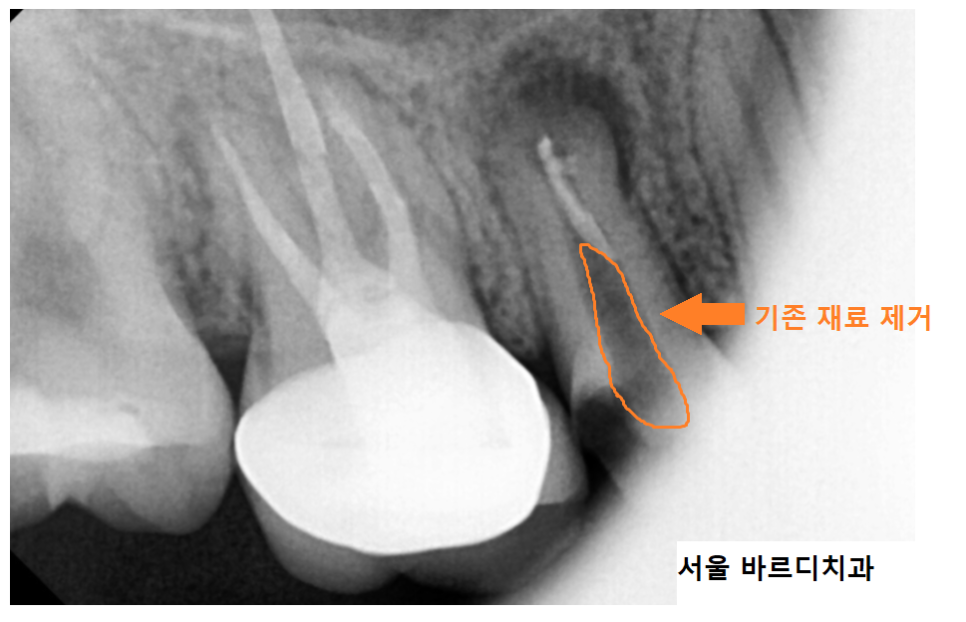

23.07.10

재신경치료는 신경치료를 다시 한다는 뜻입니다.

기존에 채워둔 재료들을 제거하고~

소독 약을 넣어 염증을 제거 하는 작업을 진행했습니다.

기존 재료를 제거하고

mta로 재신경치료 마무리 한 모습입니다.

처음 망월동 치과 방문하셨을 때는

뿌리 끝이 검정색으로

염증이 있는 상태였는데

많이 줄어든게 보이실껍니다.